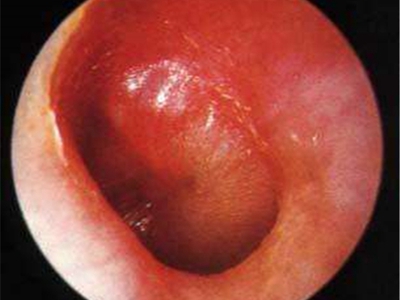

鼓膜炎又称为大疱性鼓膜炎,是鼓膜和邻近鼓膜的外耳道皮肤的急性炎症。由病毒感染所致,多发生在儿童和青年人,多为单侧,冬季多见。根据有感冒史、耳痛的症状及检查所见,容易诊断。

鼓膜炎的首发症状为外耳道剧痛,并可有轻度听力下降。随后,由于大疱破裂而有稀薄血性分泌物从外耳道流出;由于病变限于鼓膜的上皮层,未波及纤维层,故大疱破裂后无鼓膜穿孔。